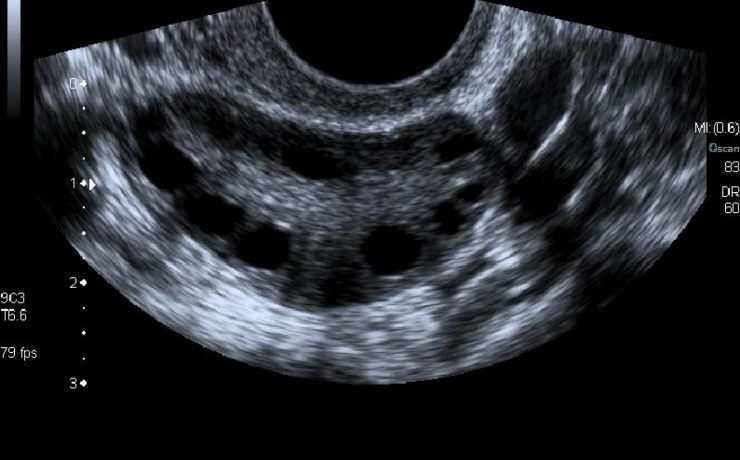

Embarazo ultrasonido en el primer trimestre

Este artículo es una muy buena forma de darnos los tips para mejorar la exploración de la paciente embarazada en el 1er trimestre del embarazo, nos hace la reflexión acerca de la interpretación de los ultrasonidos y poder realizar diagnósticos tempranamente y prevenir posibles complicaciones que ponen en riesgo la